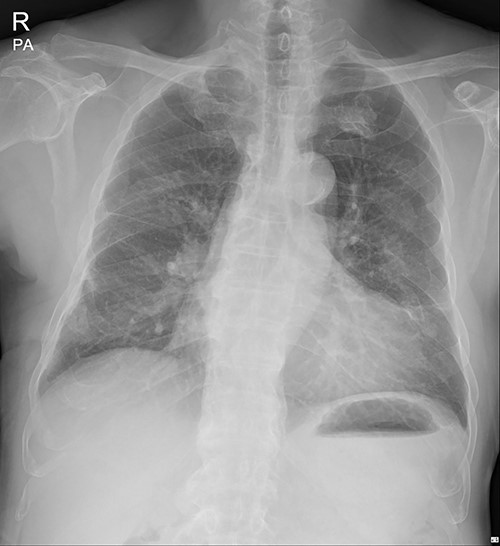

The patient visited the outpatient clinic on 07 March 2022, for stitches removal, complaining of mild discomfort on the operation site (Fig. 3.). Chest X-ray showed a large, localized submuscular emphysema between the rib cage and the SAM. The surgical wound was clear. Stitches were removed as planned, and the patient was asked to revisit the outpatient clinic 3 days later.

The submuscular emphysema, however, was increased in size, and the patient was eventually re-hospitalized. A small incision was made beneath the surgical wound under local anesthesia, and a 10 FR thoracic drainage catheter was carefully placed into the submuscular layer (Fig. 4.). Under 2 L of oxygen supplement, the submuscular emphysema gradually decreased over several days, and the patient was finally discharged on hospital Day 6 (Fig. 5). Since his last readmission, there have not been any more complications.

Chest X-ray after applying a 10 FR drainage thoracic catheter into the submuscular layer (11 March 2022).